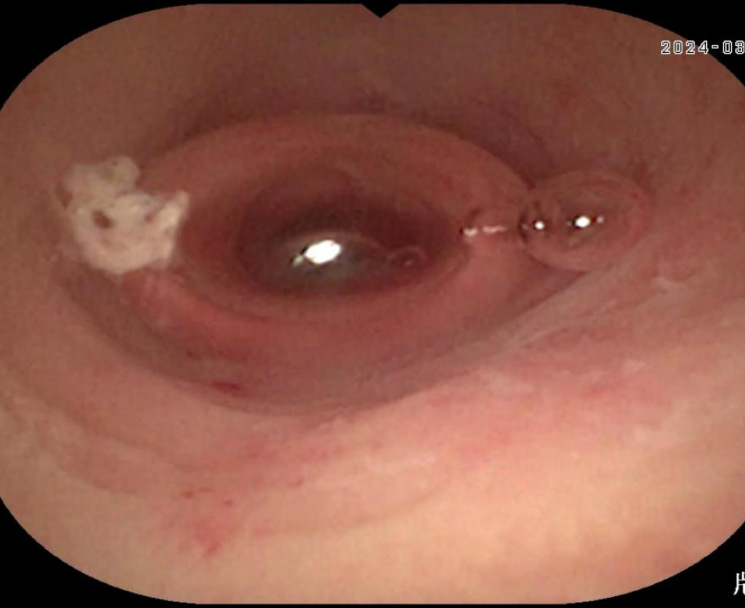

7、阑尾内支架植入引流

图片